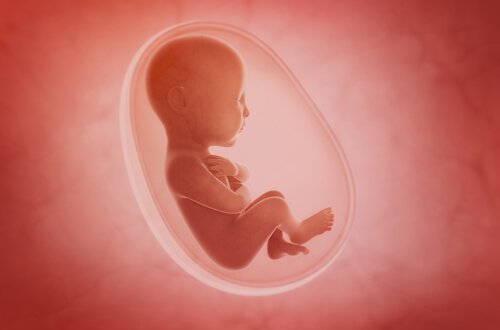

Fosterdiagnostik

Fosterdiagnostik är avgörande för både dig och din bebis för att ni ska kunna gå igenom denna process på bästa sätt. Därför har vi samlat all den här goda informationen för dig gällande medcinska tester och hur du tar hand om dig själv i varje trimester. Varje mamma förtjänar en lycklig och hälsosam graviditet.